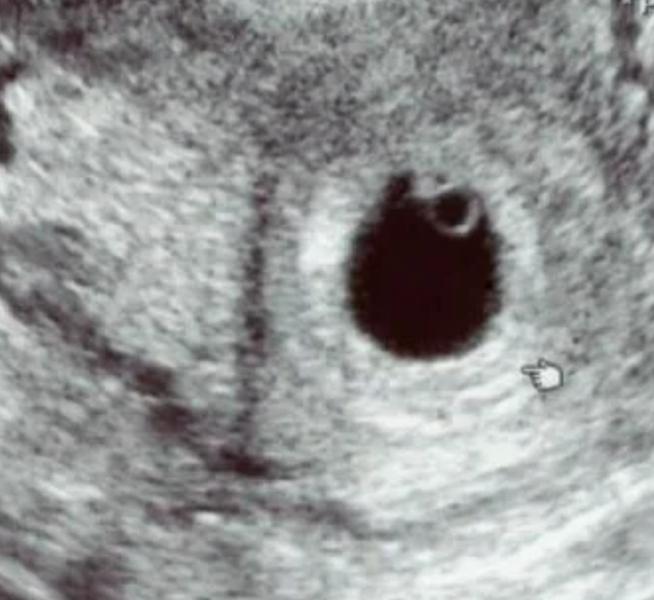

У кого есть фото с узи на первых сроках беременности, хочу проверить правда или нет что по расположению ребенка можно узнать кто будет мальчик или девочка.Или это все бред))

Мальчик и девочка, я не знаю смотрю только по месту где прикрепились , вы пол знаете?)

У меня на двух узи слева) пол скоро узнаем уже, осталось немного, потом отпишусь сюда)

Судя по узи мальчик если по картинке размещения смотреть) А вы пол не знаете?)